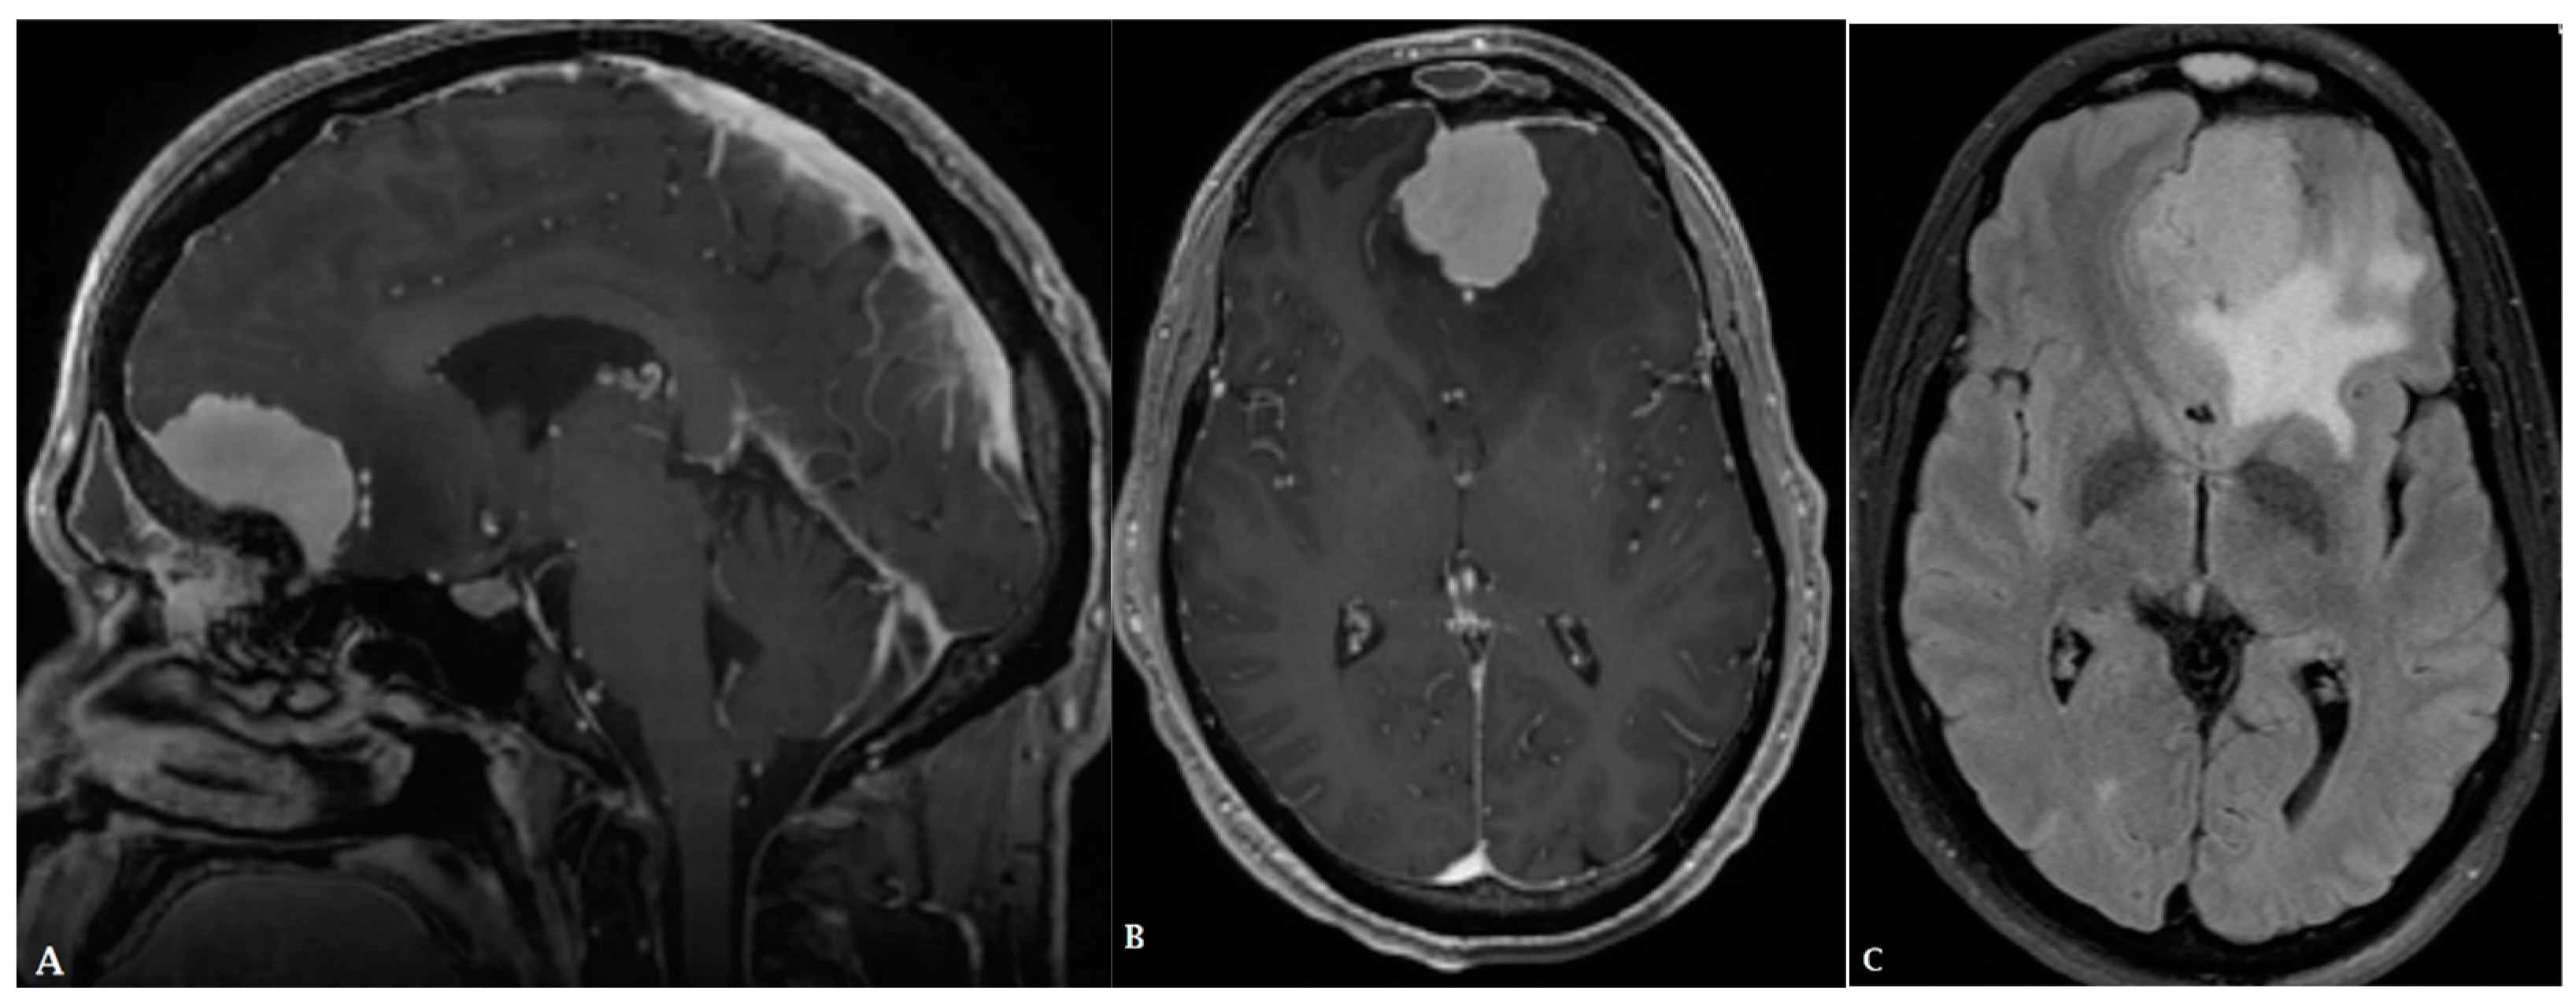

- Kickingereder, P.; Wiestler, B.; Sahm, F.; Heiland, S.; Roethke, M.; Schlemmer, H.-P.; Wick, W.; Bendszus, M.; Radbruch, A.; Jalaguier-Coudray, A.; et al. Primary Central Nervous System Lymphoma and Atypical Glioblastoma: Multiparametric Differentiation by Using Diffusion-, Perfusion-, and Susceptibility-weighted MR Imaging. Radiology 2014, 272, 843–850. [Google Scholar] [CrossRef]